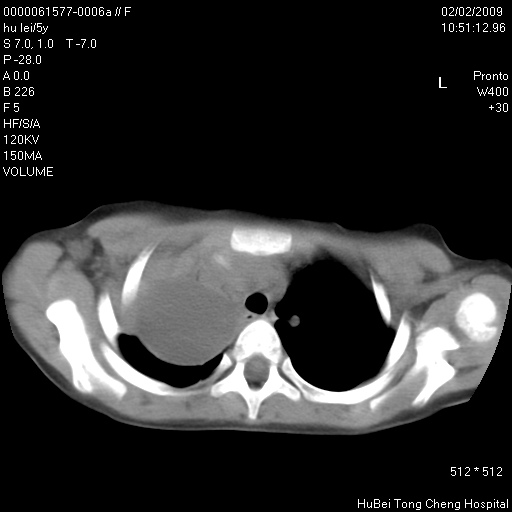

标题: PED1732:M5Y,右肺囊性占位!

患者:男,5。无明显不适,拍胸片考虑右肺囊肿。

行ct扫描,图象如下:

病灶与前胸壁和右上纵隔、叶间裂界限不清,病灶前缘及内侧缘看不到正常的肺组织,不能排除包裹性积液。